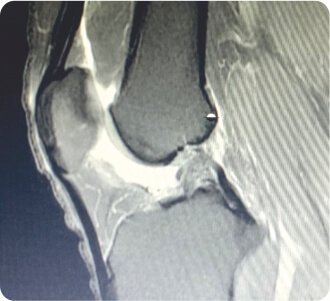

Pre-Op MRI showing meniscal tear

Pre-Op MRI showing Anterior cruciate ligament tear

X-ray showed no fractures. The Femoral tunnel was noted to be in an abnormal position. MRI showed complete ACL and medial meniscus posterior horn tears. The patient was planned for revision arthroscopic anatomic ACL reconstruction +/- medial meniscus surgery. During arthroscopy, significant laxity of the ACL and partial tear of posterior horn of medial meniscus were noted. The hamstring graft was harvested from the contralateral knee, as the ipsilateral graft was harvested during the index surgery. The graft was augmented with FiberWire for internal bracing. Old ACL remnants were cleared with a shaver. Loose pieces of old femoral BioScrew were removed. Partial medial meniscectomy was done and trimmed to stable borders. New femoral and tibial tunnels were made. Anatomic ACL Reconstruction was done and stabilised with Arthrex Tightrope RT on femoral side and BioComposite screw on tibial side. Final stability showed negative anterior drawer test. The next day, he was mobilised with full weight-bearing walking. On follow-up, he achieved full range of movements and returned to normal sporting activities.